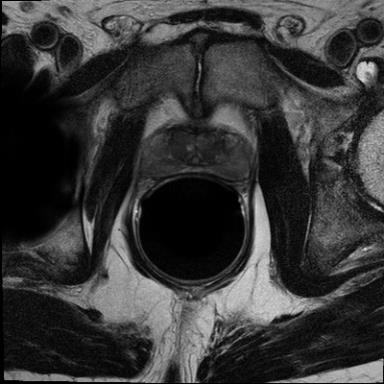

Modern deep neural networks struggle to transfer knowledge and generalize across diverse domains when deployed to real-world applications. Currently, domain generalization (DG) is introduced to learn a universal representation from multiple domains to improve the network generalization ability on unseen domains. However, previous DG methods only focus on the data-level consistency scheme without considering the synergistic regularization among different consistency schemes. In this paper, we present a novel Hierarchical Consistency framework for Domain Generalization (HCDG) by integrating Extrinsic Consistency and Intrinsic Consistency synergistically. Particularly, for the Extrinsic Consistency, we leverage the knowledge across multiple source domains to enforce data-level consistency. To better enhance such consistency, we design a novel Amplitude Gaussian-mixing strategy into Fourier-based data augmentation called DomainUp. For the Intrinsic Consistency, we perform task-level consistency for the same instance under the dual-task scenario. We evaluate the proposed HCDG framework on two medical image segmentation tasks, i.e., optic cup/disc segmentation on fundus images and prostate MRI segmentation. Extensive experimental results manifest the effectiveness and versatility of our HCDG framework.